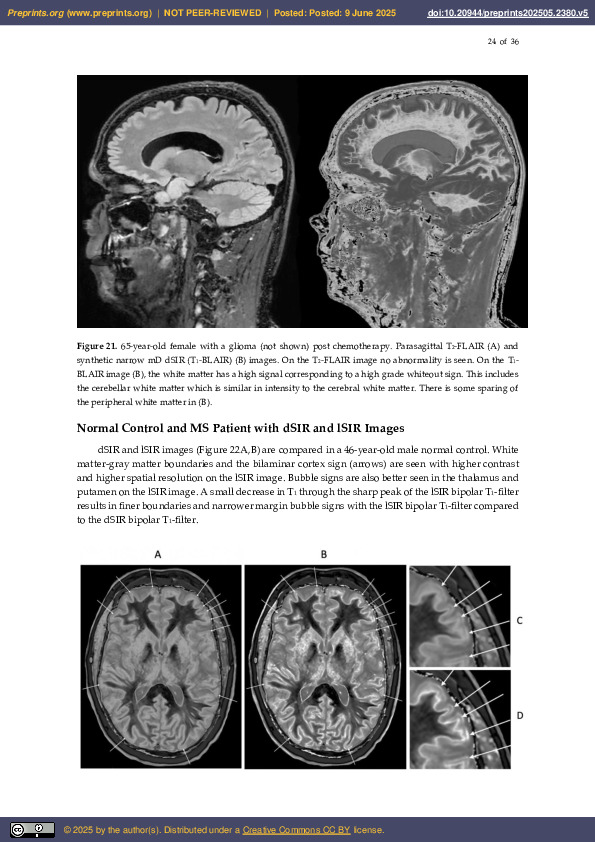

(2026). Ultra-high contrast MRI of the brain and spinal cord using directly acquired and synthetic BipoLAr Inversion Recovery (BLAIR) images. Quantitative Imaging in Medicine and Surgery, 16(1), 91. 10.21037/qims-2025-1680

(2025). Ultra-High Contrast MRI of the Brain and Spinal Cord using Directly Acquired and Synthetic BipoLAr Inversion Recovery (BLAIR) Images, Preprints. Preprints.org. 10.20944/preprints202505.2380.v5